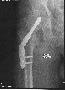

La saison est finie : fracture du col du fémur :(

Pompier, hôpital, 3 mois alités ...